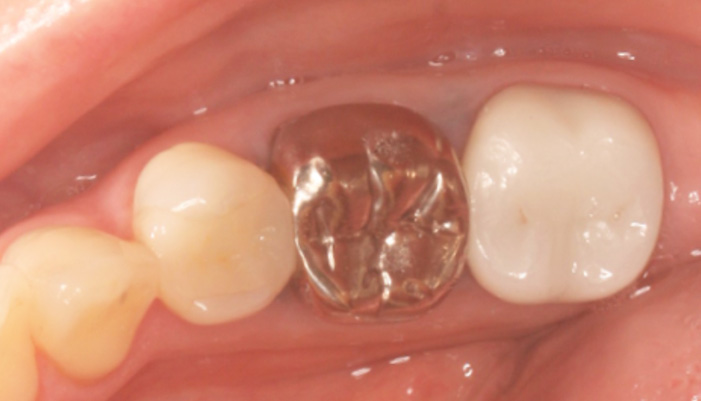

症例2

治療前

治療後

| 主訴 | 銀歯を白くしたい |

|---|---|

| 治療期間 | 2〜3週間 |

| 治療費 | ¥61,600(税込) |

| 治療内容 | 銀歯を外し、セラミックの詰め物を入れました。 |

| 治療のリスク | 個人差により、欠けたりする可能性があります。 |